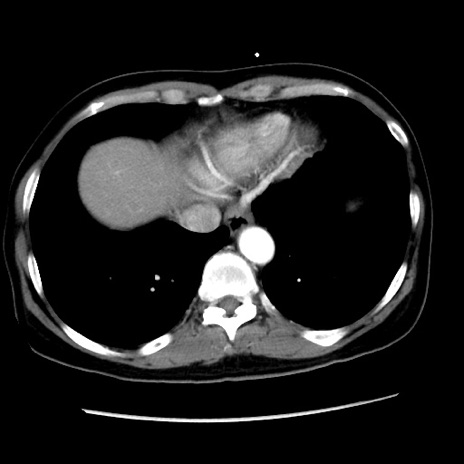

矢状断像